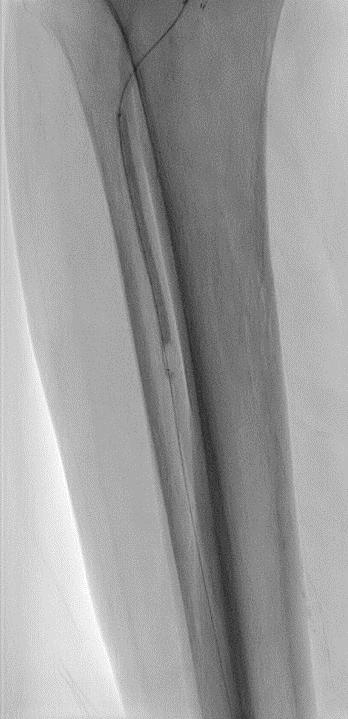

Procedural overview

Given the angiosome of the tissue loss, we elected to pursue opening the anterior tibial CTO. Access with a 5F, 70cm sheath was used from a contralateral femoral approach. Using a 0.014” microcatheter and wire escalation, we were able to cross into the true distal lumen of the distal anterior tibial circulation using a 12-gram tipped guidewire (Figure 3a). A 2.5mm Shockwave E8 was used for multiple treatments along the entire length of the CTO segment (Figures 3b, 3c). Post IVL therapy, angiography showed brisk flow through the anterior tibial and into the distal anterior circulation of the foot (Figures 4a-c). This improvement in circulation allowed for this patient to undergo her planned second toe amputation with primary close (Figure 4d).